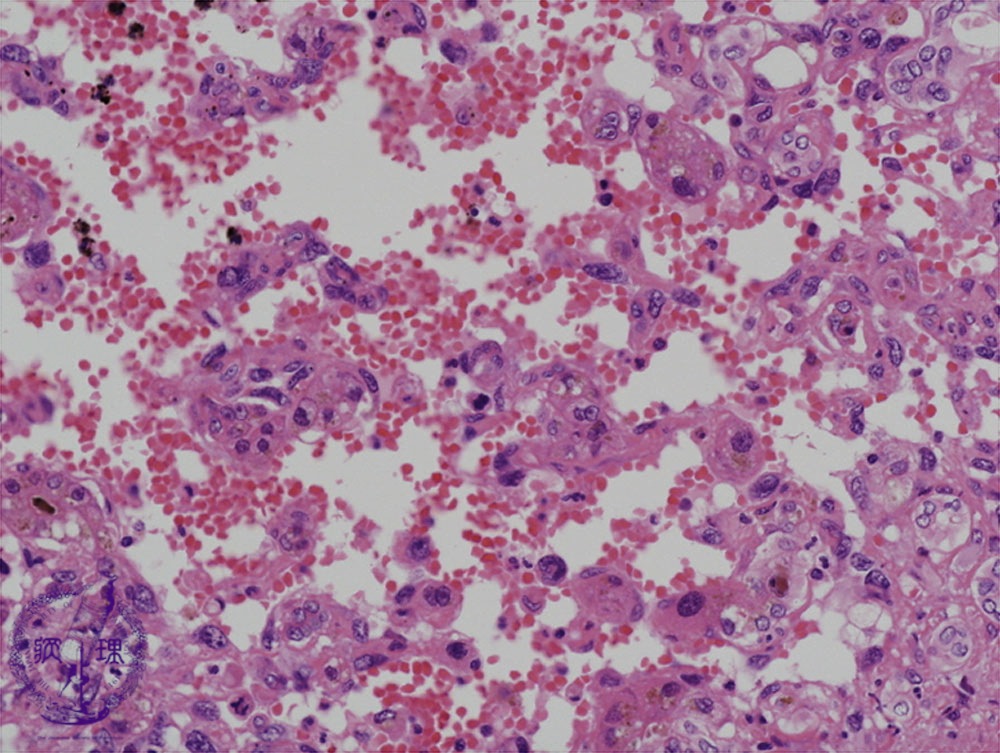

• š(14)Angiosarcoma of the liver

Microscopic image (HE stain, high power view): Tumor cells with round to slightly pleomorphic nuclei form the sponge-like tumor. Red blood cells accumulate within the intercellular spaces.